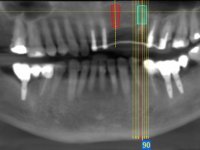

66-year-old male patient, non-smoker. It featured a 5-member metal-ceramic bridge with extreme mobility. Teeth 11 and 21 had infiltrated cervical margins. Both arches showed root exposure with signs of cervical abrasion. Composite resin “slots” were visible on the buccal surfaces of some mandibular teeth compatible with an orthodontic treatment with aligners that the patient was undergoing. After the imaging examination, it was found that the bridge's distal support, tooth 24, was irretrievably lost. The mesial pillars 11 and 21 had endodontic treatment and intraradicular posts. Teeth 25 and 26 also had endodontic treatment and extensive restorations in composite resin. In the lower jaw, two bridges were visible. In the third quadrant a 4-element bridge supported on tooth 35 and on 2 implants placed in the location of teeth 36 and 37. In the fourth quadrant a 3-element bridge supported on tooth 45 and an implant placed in the location of tooth 46. The patient presented a thick gingival phenotype and very good oral hygiene.

The patient was proposed to undergo a fixed oral rehabilitation consisting of a 2-element bridge over teeth 11 and 21 and a 5-element bridge over 3 implants that would be placed in the location of teeth 22, 24 and 26. The prosthetic structures would have an infrastructure in Zr coated with ceramic and the bridge over the implants would be screwed. The indicated extraction of teeth 25 and 26 and placement of an implant in the 26 site would imply surgery to fill the maxillary sinus. As the patient showed interest in having fixed temporary rehabilitation during treatment, we divided the treatment into 6 phases to achieve this goal: 1- Placement of a temporary bridge over teeth 11,21,25 and 26. With tooth extraction 24. 2- Placement of 2 implants in the location of teeth 22 and 24. 3- Placement of a temporary 6-element bridge over teeth 11 and 21 and over the implants. 4- Carrying out surgery to fill the maxillary sinus. 5 – Placement of the implant in the location of tooth 26 and in the area where the filling of the maxillary sinus was made. 6 – Placement of the definitive work.